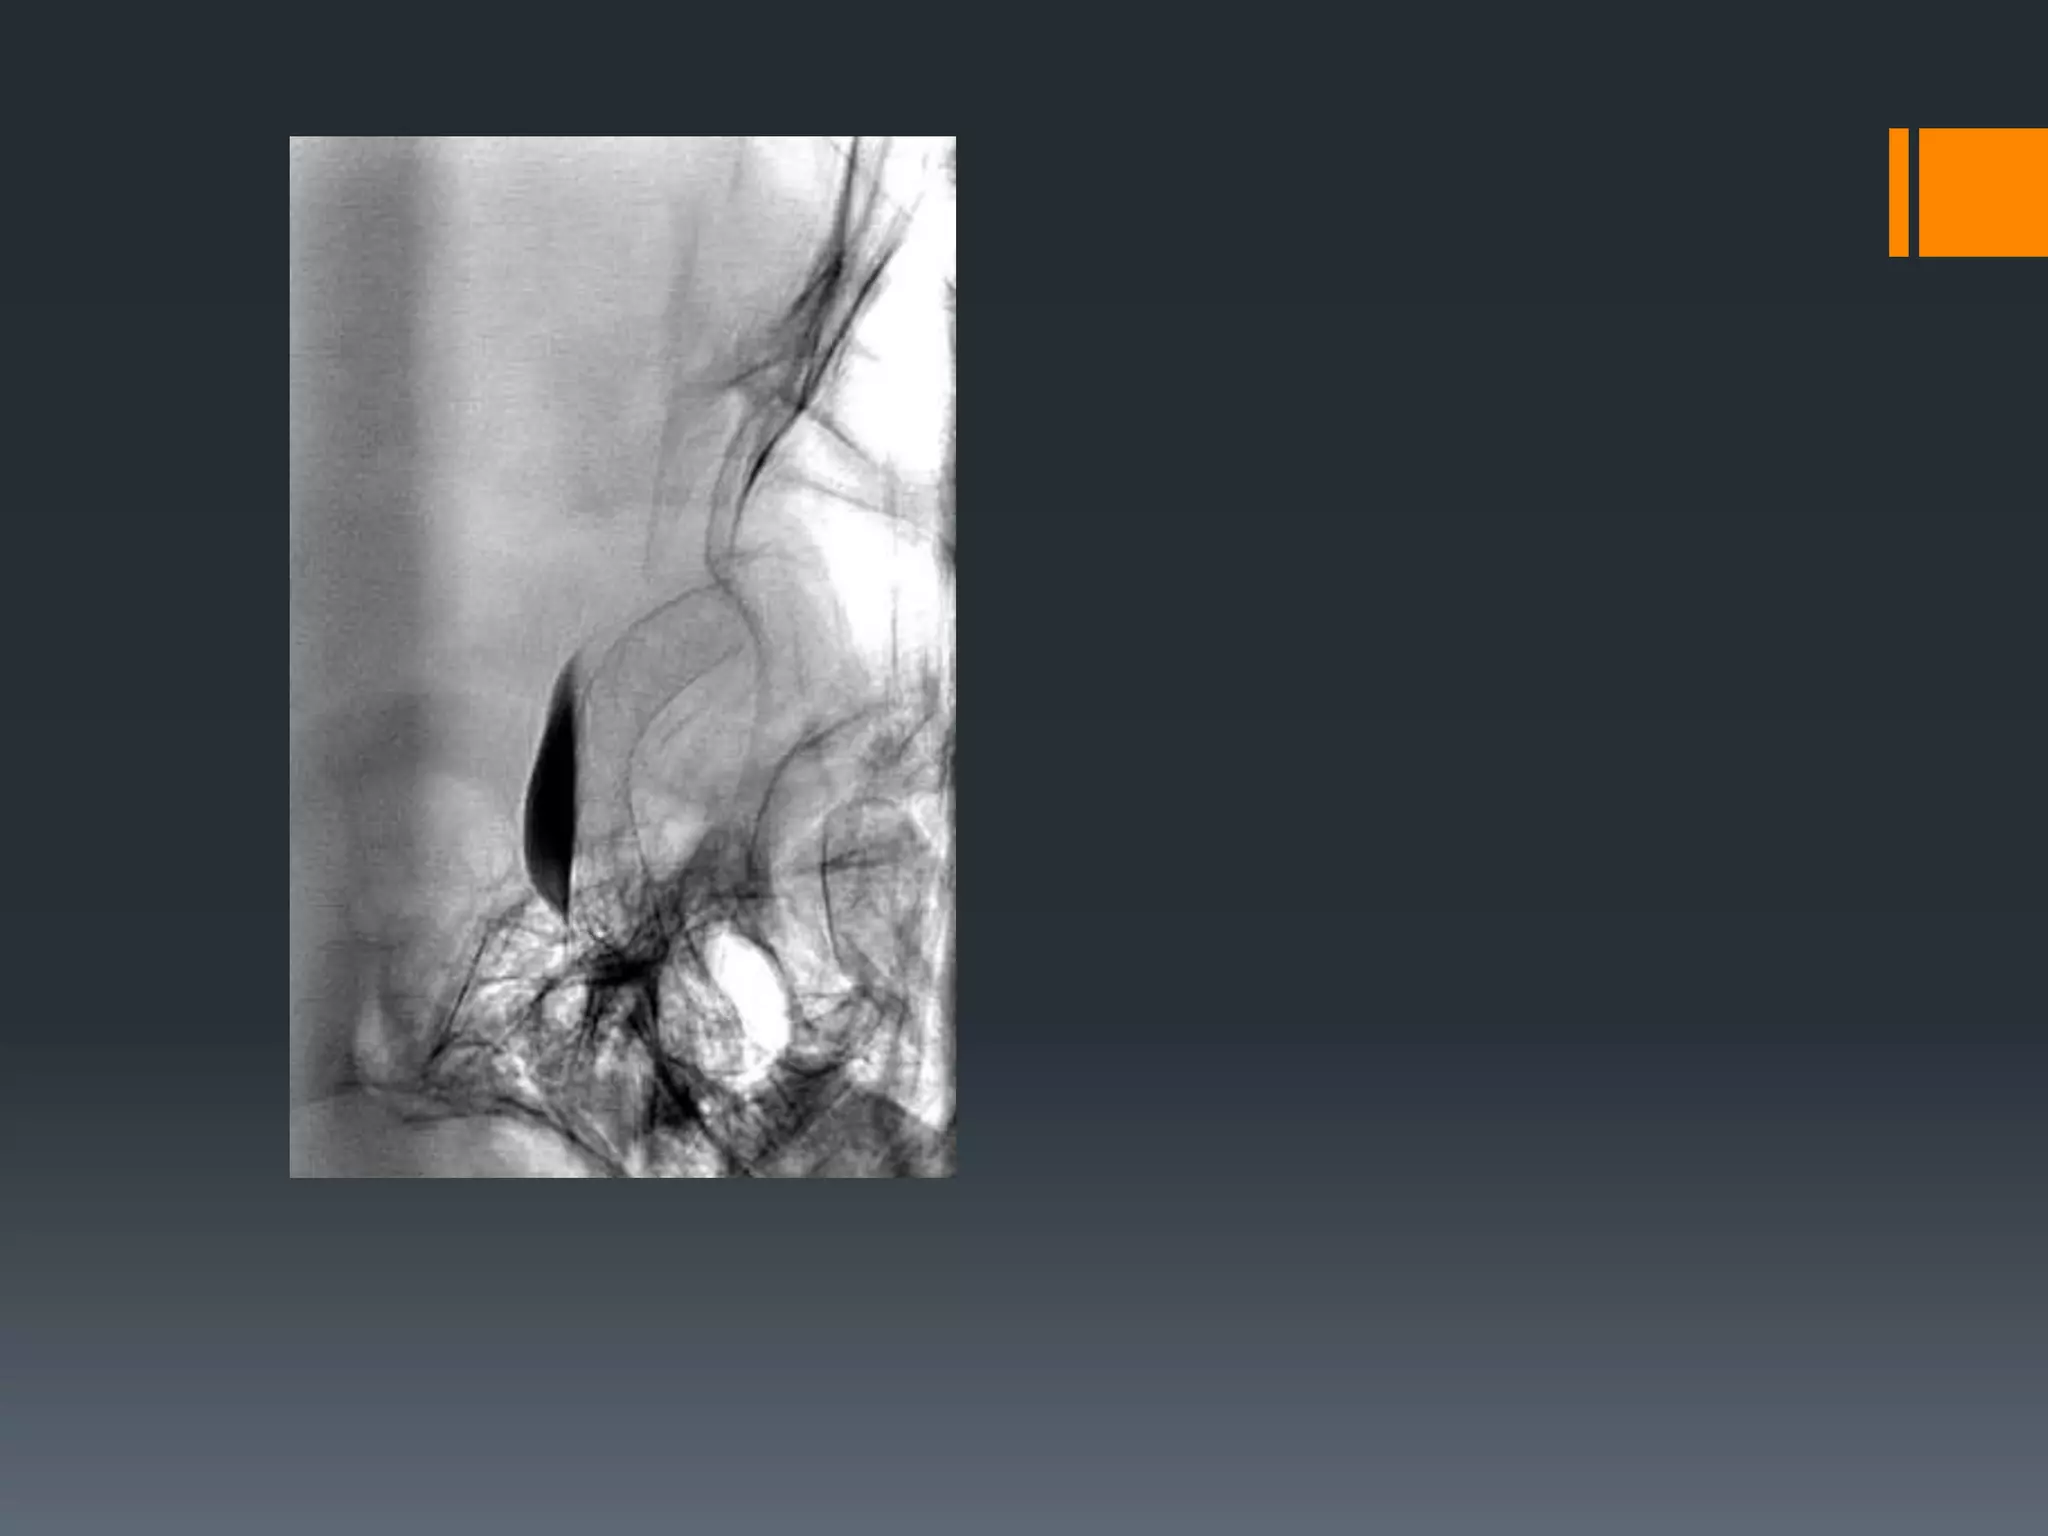

This document discusses tricks and techniques for difficult cannulations during neurointerventional procedures. It outlines strategies for accessing the aortic arch, internal carotid artery (ICA), and areas distal to aneurysms. Long sheaths, distal access catheters, and co-axial techniques are presented as options that have improved cannulation success. Guidance on sheath and catheter selection is provided for different vessel paths. The importance of catheter placement as high as possible in the ICA is emphasized. Reverse curve cannulations are also mentioned. Overall, the document stresses that careful cannulation is critical for procedural success and different strategies may be needed depending on the vessel target.